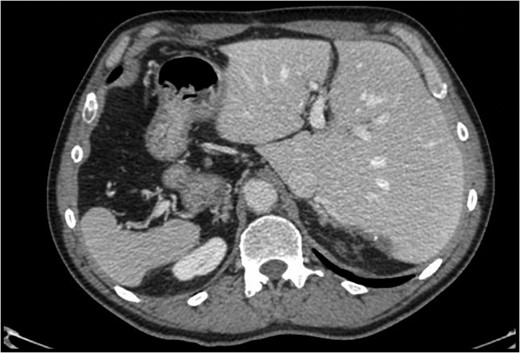

Situs inversus totalis (SIT) is a congenital condition consisting of a mirror image of transposition of the abdominal and thoracic organs occurring in about 1:5000 to 1:10 000 adults. We report on a 60-year-old male with a single colorectal liver metastasis in the Segment 7. The patients underwent a totally laparoscopic sub-segmentectomy. Intraoperative approach on a reverse posterior segment was difficult because of left-sided position of the liver. Postoperative course was uneventful and the patient was discharged after 5 days. To our knowledge, only a few cases of open liver resections in patients with SIT have been published. This is, therefore, the first case of laparoscopic liver resection for colorectal liver metastasis in a patient with SIT. We provide the readers with useful tips to perform minimally invasive liver surgery in such patients.

Situs inversus is a congenital condition with an incidence ranging between 1:1000 and 1:10 000 characterized by left-to-right transposition of one or more normally asymmetrical organs of the body. Situs inversus totalis (SIT) consists of a mirror-image transposition of the abdominal and thoracic viscera, which occurs in about 1:5000 to 1:10 000 adults [1]. Patients affected by SIT are usually completely asymptomatic, but they have more commonly major defects which can shorten their lifespan [1].

These observations are even more true for a patient with previous open surgery and an SIT with the double challenge related to the anatomic position of the liver and the posterior (7) segment involved. Another challenging maneuver was the separation of the liver from the diaphragm; the absence of any ligament made this part of the procedure very demanding to identify the correct plane from the diaphragm and the liver and minimize the bleeding.